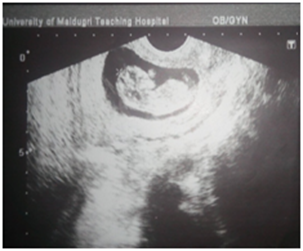

Abdomino-pelvic ultrasound scan revealed an intrauterine viable gestation of 13 weeks with 5 days old as shown in Figure 1A, there was also dilatation of the pelvicalyceal system involving the proximal part of left ureter and presence of 2 calculi within the left renal pelvis, the larger one measured 1.6cm in size as shown in Figure 1B and the right kidney was normal. Serum electrolytes, Urea and Creatinine including urinalysis, urine culture and full blood count were normal. She was then planned and had urethrocystoscopy and Double J stenting of the left ureter under general anaesthesia as shown in Figure 2A. Cystoscopic findings were minimal resistance while stenting the left ureter, which was ultimately, overcame, otherwise normal bladder mucosa and ureteric orifices and no stones within the bladder. Postoperative condition was satisfactory and symptoms subsided. She was later discharged home on oral antibiotics. Since then, she has been regular with her follow up and has been doing well until when she was re-admitted with an assessment of anemia in pregnancy secondary to Malaria and Urinary Tract Infection (UTI) at 32nd week gestation. She responded well to antibiotics and antimalarial, and also had blood transfusion. The serial electrolytes urea and creatinine remained normal. The pregnancy was monitored till term and had spontaneous delivery of normal female neonate weighing 3kg. Patient was re-evaluated in the first week of puerperium, the findings from the repeated abdominal ultrasound scan and KUB were 2 left renal calculi, and one of them has already enlarged to a bigger size of 2.5cm in its widest dimension and presence of intact left ureteric double J stent, otherwise no soft tissue or bony abnormalities seen. She later had left Nephrolithotomy and extraction of double J stent. Intra-operative findings were ‘’stag horn calculus’’ with another small calculus in the left renal pelvis as shown in Figure 2 (B & C). Post-operative condition was satisfactory and was later discharged home. The metabolic evaluation and stone analysis revealed calcium oxalate and calcium phosphate and she was counseled on dietary calcium.

Figure 1(B) USS of left renal calculi.